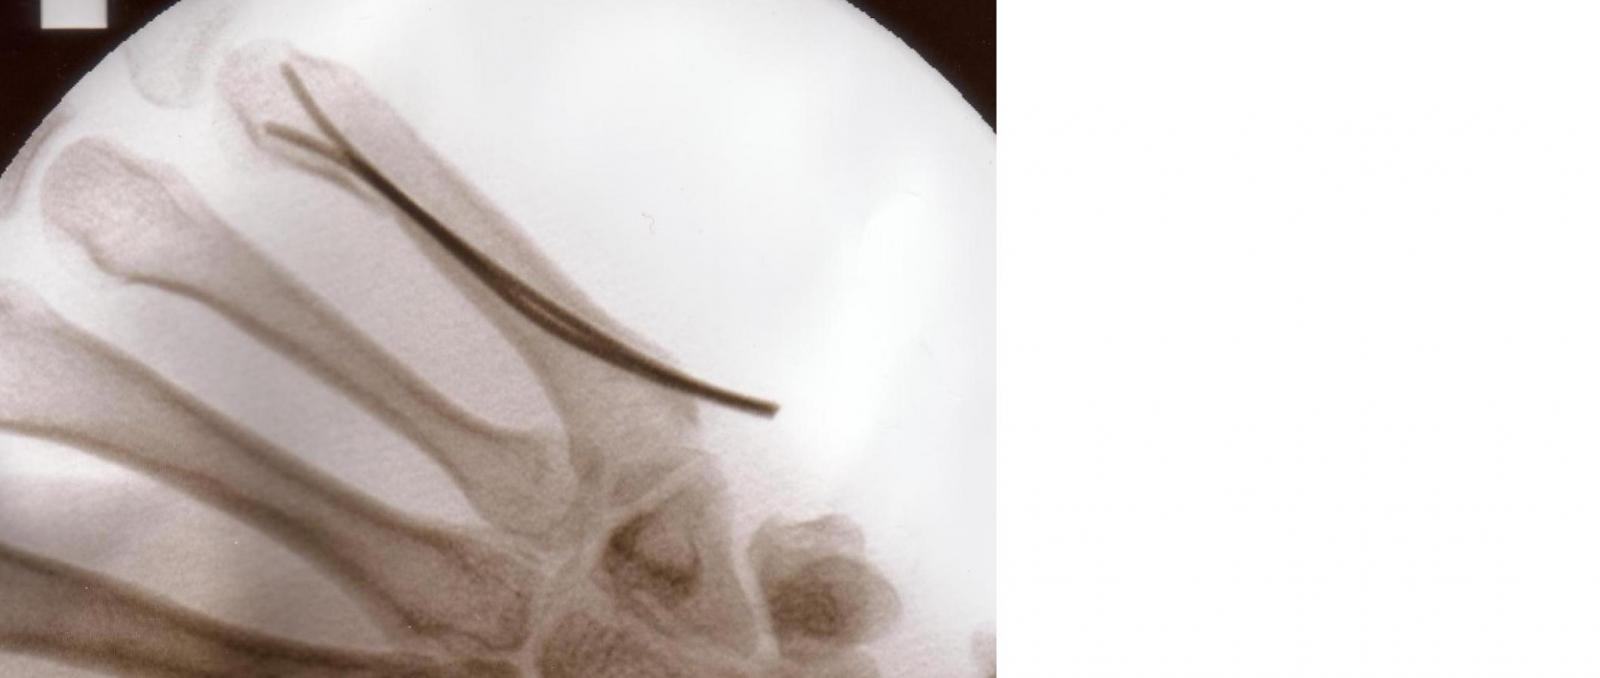

Was ein vergleich der Verteilung von Wärmeleitpaste auf Referenzkühler und Morpheus II Core Edition aussagt.

Morpheus: Anhang anzeigen 417227

Referenzkühler:Anhang anzeigen 417228

Vermutet wird das der Morpheus II Core Edition einen leicht konvexen schliff hat, wenn das so ist hat das gute Gründe und wäre kein Mangel!